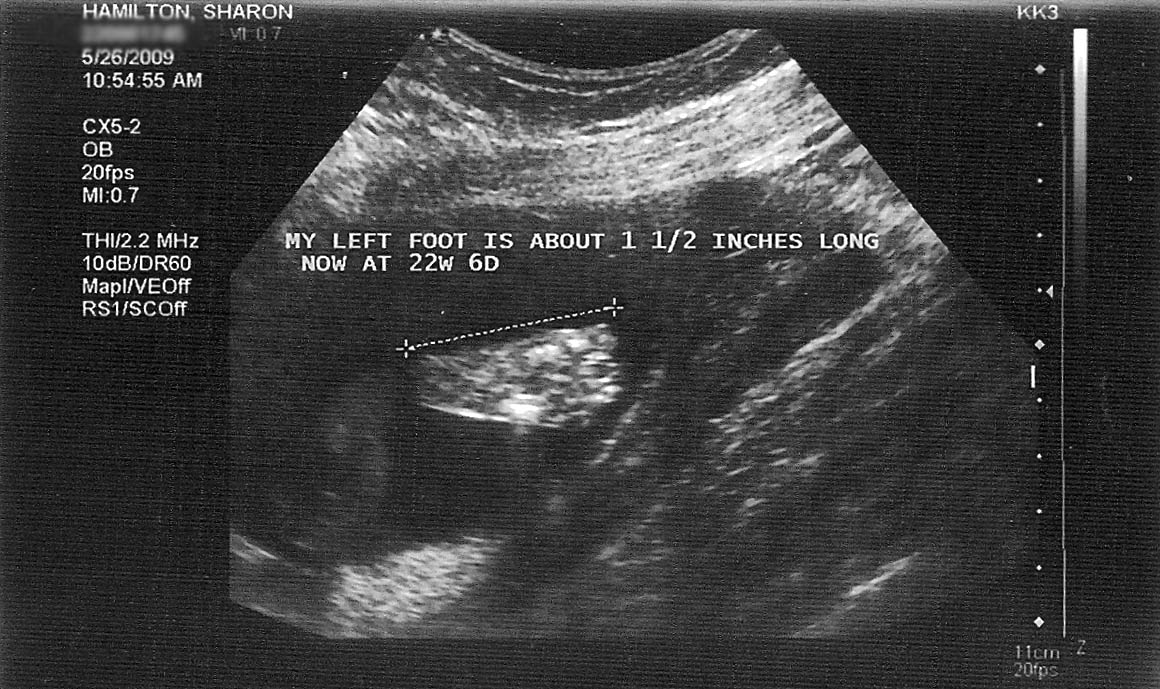

We had another ultrasound and checkup yesterday to monitor the progress of Nora and the pregnancy. All is going well, nothing much to report which is a good thing at this point. “No Gnews is good Gnews”. (anyone know where that quote is from? 🙂 But one thing we have been increasingly noticing with Nora is that she moves alot. She gave the ultrasound tech a run for her money when she was trying to examine her and take measurements. It is so cool to watch her move in there. She used her hands to shield her face at times, she kicked at the probe. It was quite amusing. But on the other hand, is this a precursor to what is to come. Is she going to be a restless child and not sleep a lot, instead always wanting to play and be doing stuff? Not sure if the movement in the womb equates to how they are as babies. If anyone has an experience to share or knowledge on the subject I would be curious to hear about it.